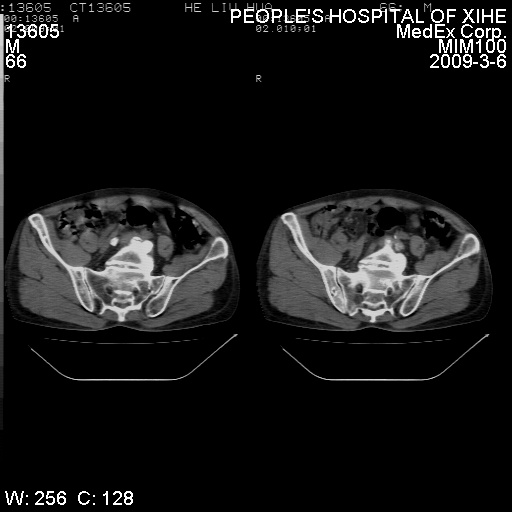

标题: CT18522:男,66岁。考虑结核有错吗 [打印本页]

标题: CT18522:男,66岁。考虑结核有错吗

x线片示:骶骨密度增高。

考虑----腰椎骶化-----退变-----椎管狭窄

腰骶椎退行性改变。

腰骶椎退行性改变,建议重建看看!

退行性变,椎体滑脱

腰椎滑脱并有退变

退行性变,椎体滑脱。建议同椎体平行进一步扫描。